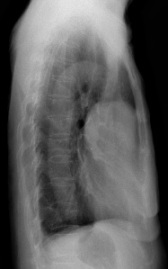

病历摘要:胸腺瘤患者,女性,55岁,重症肌无力多年,发现贫血1年余。查体.双侧眼睑下垂,面色苍白。行胸部平片检查。